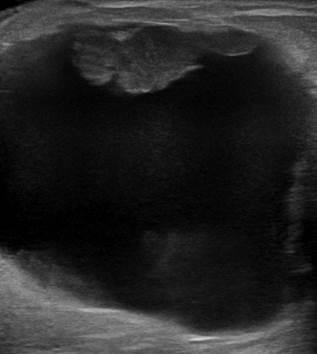

Ung thư vú

Ung thư vú - Ảnh 2

» Thông tin: Nữ giới – 85 tuổi.

» Lâm sàng: Khối tuyến vú.